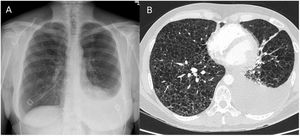

We present the case of a 43-year-old non-smoking woman, with no relevant medical history, who was treated in our emergency department due to progressively increasing dyspnea in the last year, more accentuated in the last month, accompanied by occasional cough without expectoration and atypical chest pain. On examination, she presented good general condition, hemodynamically stable, and basal SaO2 of 95%, with bilateral hypophonesis standing out on respiratory auscultation. In the laboratory tests requested, no noteworthy alterations were observed, except for severe hypoxemia with hypocapnia (basal ABG: pH 7.43; pCO2 31mmHg, pO2 65mmHg, HCO3 22mmoL/L, lactic acid 0.7mmol/L). The imaging tests that were performed are attached below (Fig. 1). The chest X-ray revealed a mild left pleural effusion and the chest AngioCT showed countless pulmonary cysts distributed throughout the lung parenchyma with associated left pleural effusion.